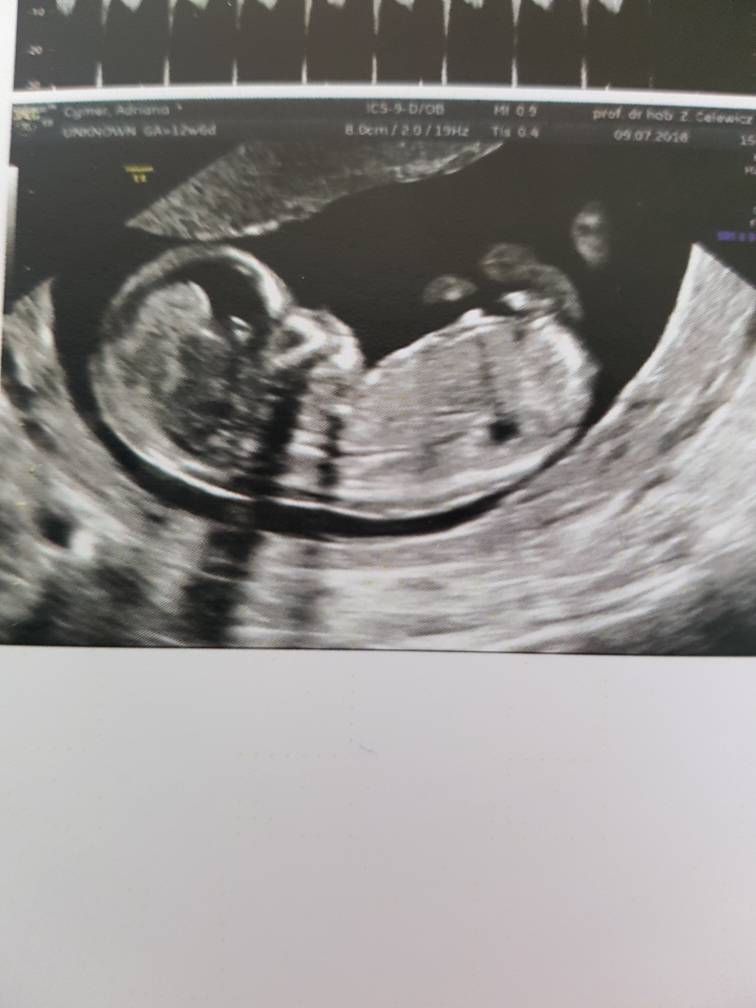

Mam 6.51cm taki już duży jestem :-)

Pięknie machałem do mamy i taty i ładnie współpracowałem z Panią doktor :-)

Pani doktor powiedziała, że wyglądam jej na chłopca i by się bardzo zdziwiła jeśli okazałoby się, że jestem dziewczynkątakże jak na razie zostaję Mateuszkiem[emoji170] [emoji7] Co mamie się zgadza bo tak czuje[emoji12]

na USG wszystko w porządku, jeszcze tylko trzeba poczekać na wyniki z krwi ale mama jest dobrej myśliZobacz załącznik 875479Zobacz załącznik 875480